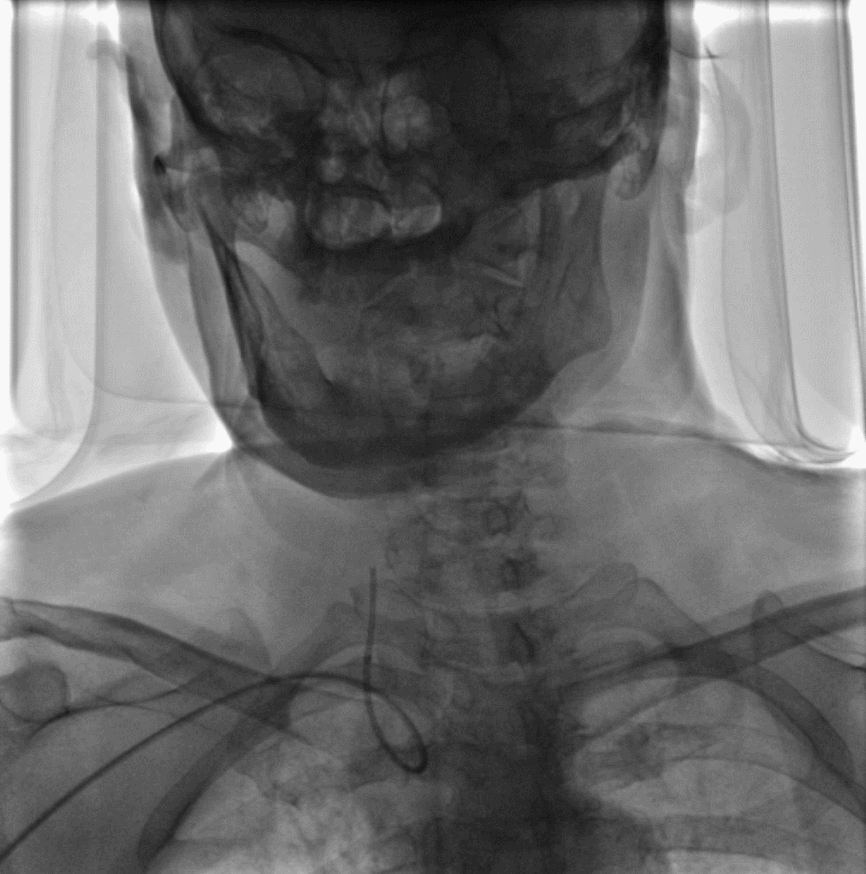

术后成形良好

输送950Wallstent支架过程中系统稳定未出现移位

撤除内衬后088薄壁长鞘保持稳定未打折